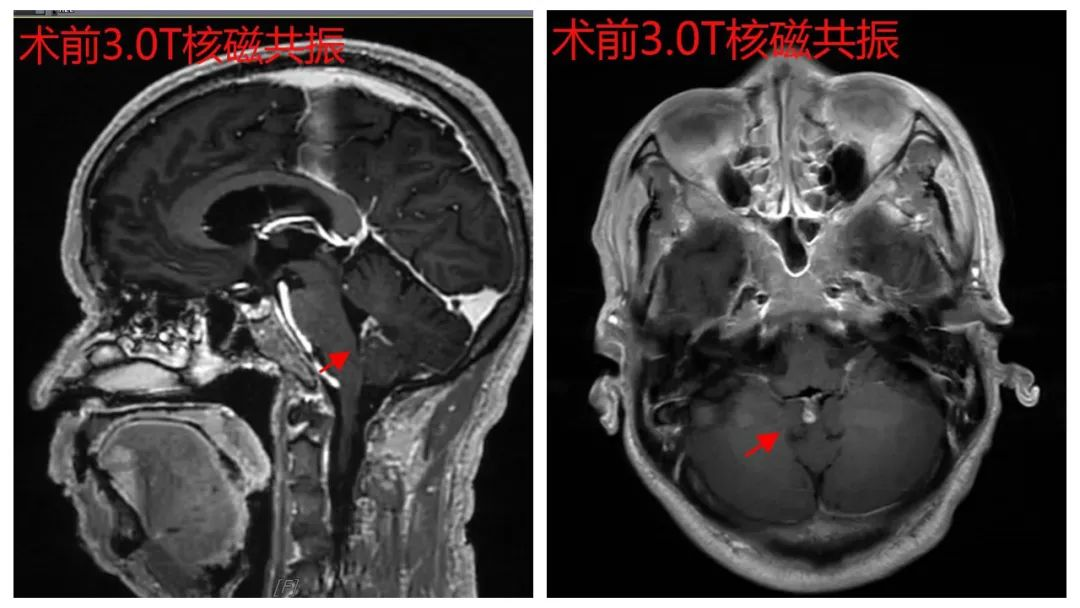

患者男性,65岁,因“头晕、头痛16小时”入院,入院CT提示小脑出血,进一步完善颅脑CTA及颅脑3.0T核磁共振后,考虑诊断小脑蚓部动静脉畸形出血,进一步全脑血管造影后,确诊为小脑蚓部动静脉畸形(b-AVMs)合并动静脉瘘(AVF),病变位于后颅窝,位置深,靠近脑重要结构(脑干),脑血管病变复杂,颈部血管、供血动脉迂曲,供血动脉细小;且患者经济贫困,未购买任何医疗保险。患者病情危重,病变部位随时可能再出血,危及生命安全,需尽快手术治疗。经科内讨论,并将患者情况向我科客座教授、广东省人民医院知名神经外科专家陈光忠主任医师汇报后,陈光忠教授指示:开颅手术创面大、损伤多,老年患者易发生并发症,且住院时间长,治疗费高;神经介入治疗创伤、负损伤小,住院时间短,费用少,建议采取介入治疗。

术前3.0T核磁共振影像资料(箭头所指为病灶)